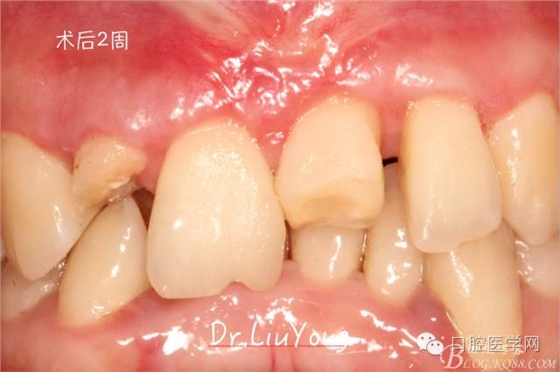

術(shù)后兩周,復(fù)查,A1達(dá)到了完全的根面覆蓋,B1牙齦退縮由原來(lái)的3.5mm減少到1mm,B2近中牙齦也得到部分的恢復(fù),同時(shí)所有牙齦邊緣都通過(guò)手術(shù)增厚。如上圖